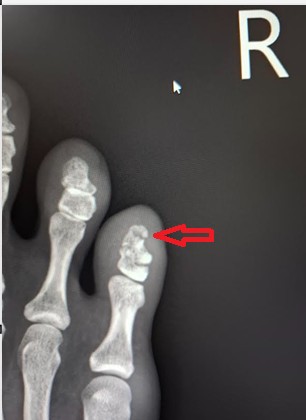

วันที่ 1 กย. 68 นิ้วบวมแดงไม่หายเลยไปหาหมอ X-ray พบว่ากระดูกปลายนิ้วแตกตามรูป หมอให้ทำ Buddy taping